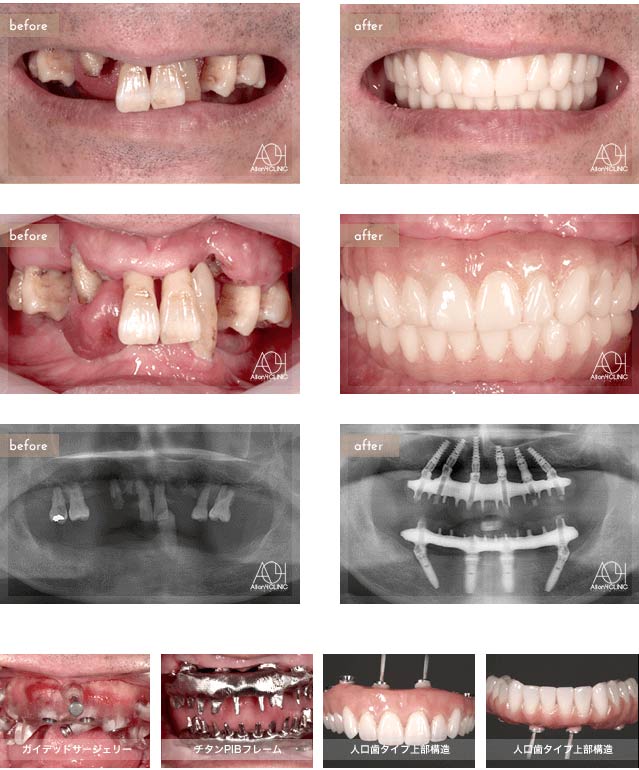

Treatment : All-on-4

- Upper All-on-4

- Lower All-on-4

Age : 62 Sex : 女 Y.M

| 主訴 | 入れ歯が合わなく痛いし、入れ歯を入れている事が嫌になってしまった。 |

| 治療内容 | X-guide(エックスガイドナビゲーションシステム)を用いてインプラントを正確に埋入。 上下オールオン4。 |

| 治療費(総額) | ¥7,200,000(税抜)『モニター割引適用』 |

| リスク | 治療後の口腔管理が不適切な場合、埋入したインプラント周囲に感染・炎症を起こし、脱落する可能性がございます。 |